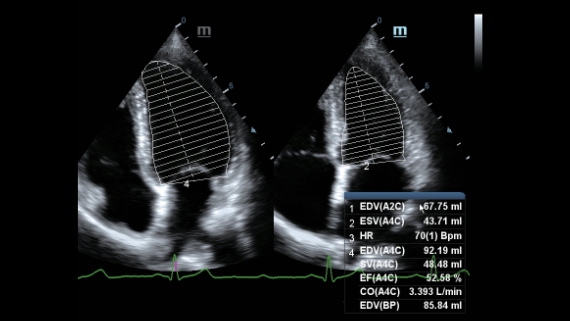

X-Insight is een inzichtelijke oplossing om meer visie te krijgen.

De gloednieuwe oplossing van Mindray is het geslaagde product dat is voortgekomen uit voortdurende klantinzichten in klinische behoeften in combinatie met steeds evoluerende, geavanceerde ultrasoundtechnologie?n. Vol energie en gebrand op toekomstgerichte inzichten en eindeloze mogelijkheden: dankzij de verhoogde schaalbaarheid wordt de oplossing continu verbeterd.

De DC-60 Exp met X-Insight is ontworpen op basis van diepgaand inzicht in klantbehoeften om hoge effici?ntie met nauwkeurige beeldverwerking te leveren, dankzij eXacte helderheid, eXceptionele intelligentie en eXcellente ervaring.